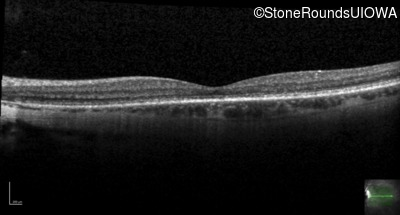

Optical Coherence Tomography - Left - 20/40

Exemplar / OCT Stack

OCT Stack